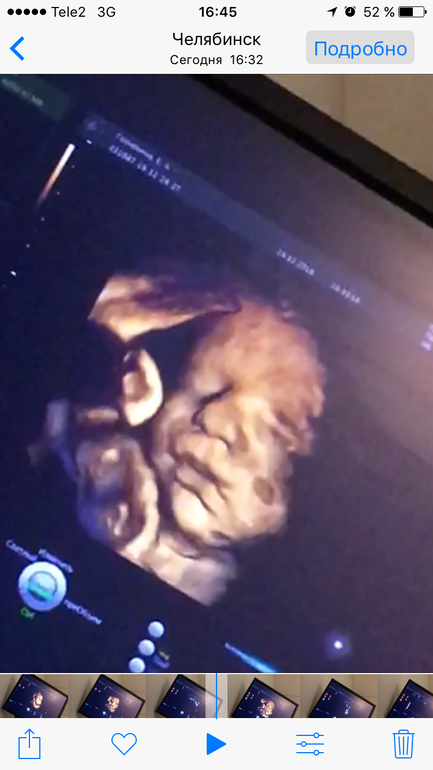

Там движение вам покажут в обычном 2д,а в 3д фотку просто сделают))вот сегодня была-29ая

уже видно,что на старшего сына похож только носом😂не похожи,хотя родные братья